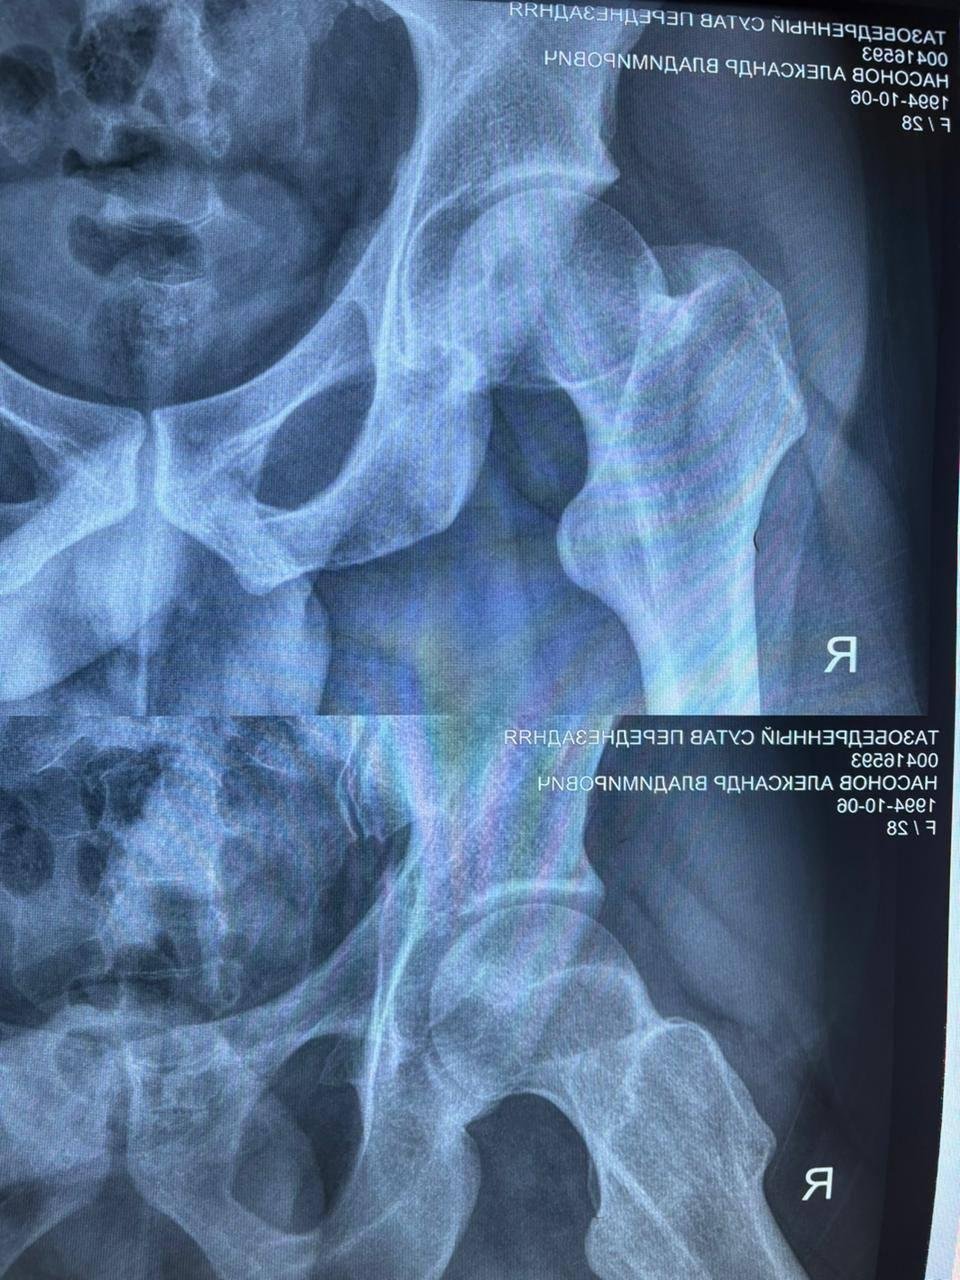

Звучит сложновато, так что вот картинка как выглядит жопа автора (а вы за это еще и заплатили)

Цитата одного из врачей когда он посмотрел снимок

Я вижу серьёзные изменения сустава. Причина, вероятно, в юношеском эпифизеолизе в детстве или в асептическом некрозе. Сейчас уже выраженные вторичные изменения, если сустав болит, то надо думать об эндопротезировании.

В 27 лет я снова сделал снимок, сходил к врачу, и он сказал, что эндопротезирование точно нужно будет делать, но давай хотя бы после 30, а лучше ещё позже (он был прав).